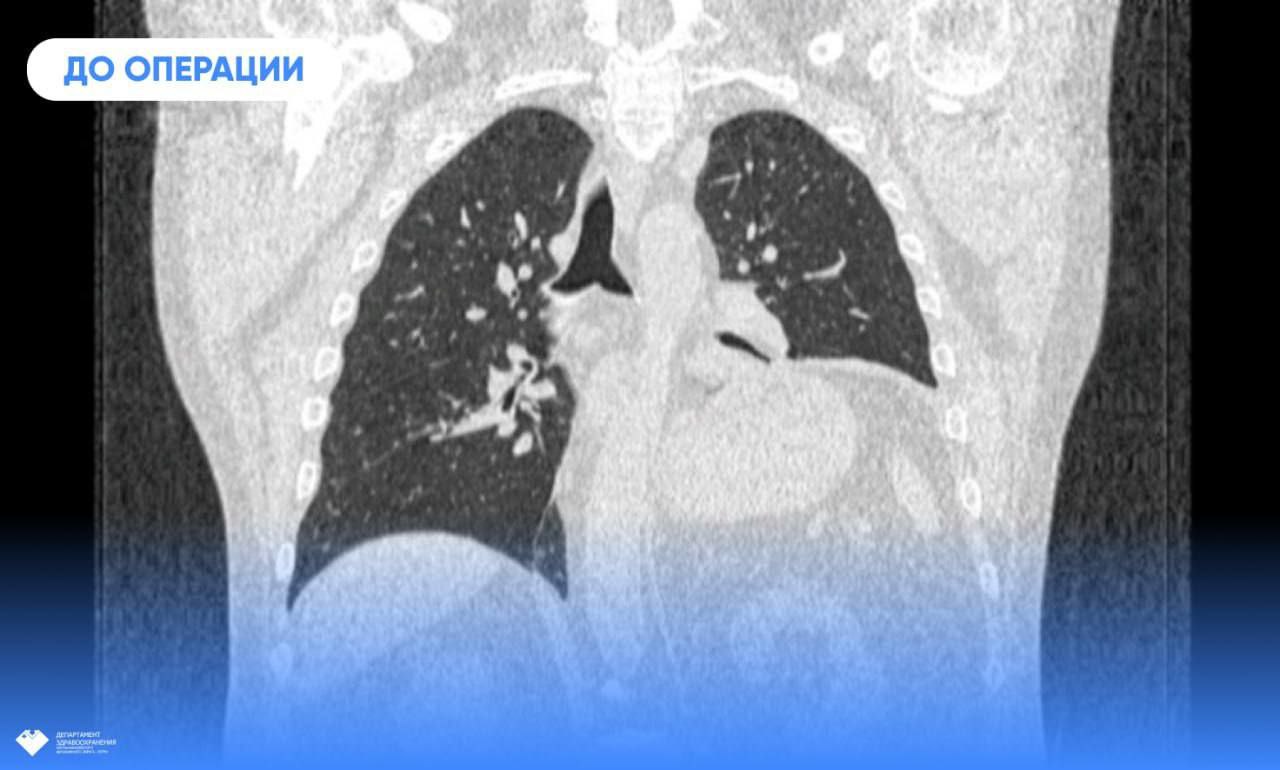

Проблемы со здоровьем сургутянин Юрий Шавров распознал по сильной одышке. Мужчина буквально задыхался при малейших физических нагрузках. Как выяснилось при обследовании, его левое лёгкое значительно уменьшилось в объёме и не может полноценно выполнять свою функцию. И всё потому, что его сдавливает диафрагма.

Релаксация купола диафрагмы – состояние, при котором он утрачивает способность сокращаться. В основе патологии - повреждение диафрагмального нерва. К таким последствиям приводят воспалительные процессы, вирусные инфекции, травмы, нарушение мозгового кровообращения, операции. И всё же при большом разнообразии причин заболевание считается довольно редким.

Расслабленная мышца не способна сопротивляться отрицательному давлению плевральной полости, поэтому под его действием поднимается выше обычного, притесняет лёгкое и не даёт ему расправиться.